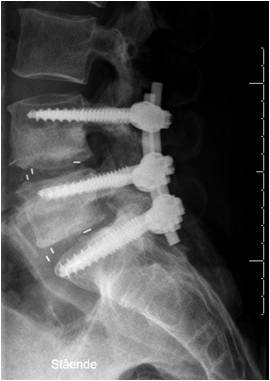

Nu fortages der et snit i huden i midtlinien . Med et skarpt instrument løftes rygmusklen til side og væk fra ryggen. Torntappen og den bageste del af ryghvirvlen, hvirvlebuen, blotlægges. Vejledt af røntgengennemlysning isættes kraftige titanium skruer i (pedikelskruer) i hvirvelbuen på begge sider gående ned i hvirvellegemet. Kirurgen kan herefter afhængig af behovet fjerne torntappen, hvirvelbuen og det såkaldte gule ledbånd som forbinder ryghvirvlerne bagtil, dette skaber et vindue og bedre plads i rygkanalen til nerverne.

Hvis det er nødvendigt kan kirurgen også åbne op ud i rodkanalerne. Pladsforholdene bliver gennemgået grundigt med en krog. Rygkanalens indhold skubbes forsigtigt til den ene side. Herefter kan man se direkte ind til båndskiven og diskus. Diskusrummet åbnes med spids kniv og herefter udtømmes diskus-materiale. Hvirvellegemets endeplader gørtes klar til blødende knogle. Derefter isættes en kile, kasse, i passende størrelse fyldt med knogletransplantat, Diskusrummet fyldes ligeledes med knogletransplantat. Der monteres skinner som forbinder skruerne fra et niveau til det næste. Yderligere knogletransplantat lægges ned på siden af rygsøjlen.